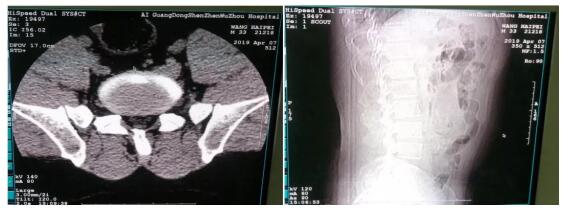

上图为王先生腰部CT拍片影像

第二天王先生坐着轮椅在家人的陪同下走进了深圳五洲医院,入院后经过CT检查被诊断为“腰椎间盘突出”。